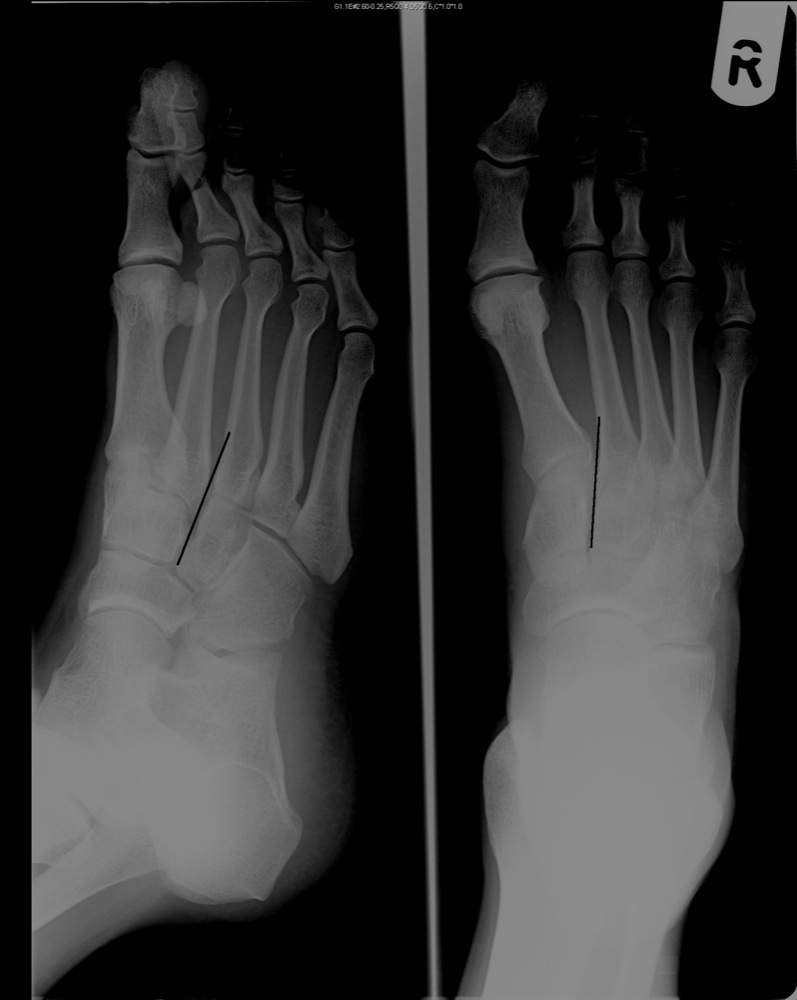

Foot xray image AP and Oblique view isolated on black background Stock X Ray Ap View Foot Align and center long axis of foot to cr and to. The anatomic position is with the hands supinated (palms forward). Patient standing in angle and base of gait with weight evenly distributed between the two. This article relates mainly to traumatic injuries to the foot. First, scan the whole image and find what you can. A basic review should. X Ray Ap View Foot.